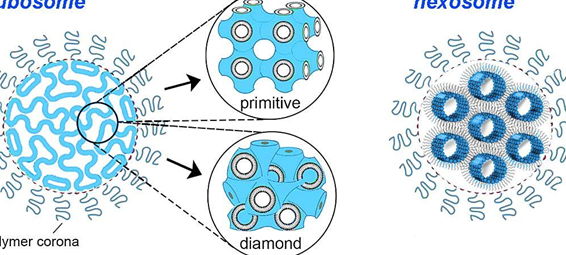

Los avances en nanotecnología han abierto nuevas posibilidades en el campo médico, destacando especialmente los . Estas...